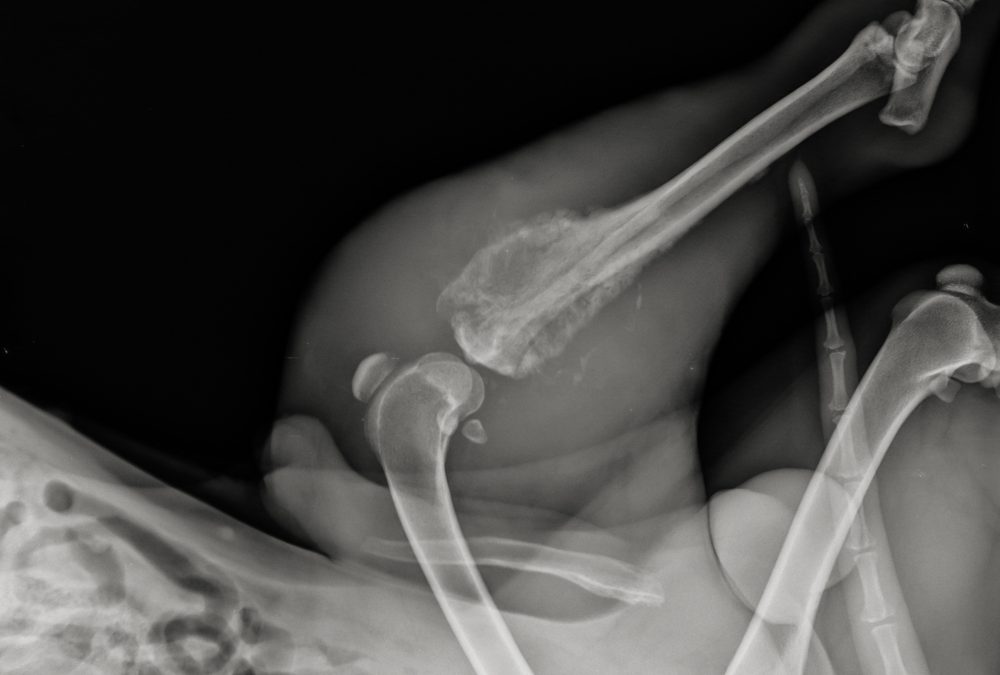

Researchers at the University of Colorado Cancer Center are investigating a new strategy to prevent osteosarcoma from spreading to the lungs, the most common and deadly site of metastasis. Veterinary oncologist Dan Regan, DVM, has received a long-term NIH R37 MERIT Award to study a novel drug combination targeting the lung “metastatic niche.” Working with medical oncologist Breelyn Wilky, MD, Regan is focusing on fibroblasts, connective tissue cells that can be hijacked by cancer to promote tumor growth and spread.

The team will test a fibroblast-targeting drug that inhibits focal adhesion kinase (FAK), a signaling pathway hyperactivated in osteosarcoma tumors and their surrounding microenvironment. Combined with standard chemotherapy, the FAK inhibitor aims to both kill cancer cells and disrupt conditions that allow metastasis. The research will be conducted in dogs with naturally occurring osteosarcoma, accelerating translational insights that may ultimately benefit human patients with this rare but aggressive cancer.